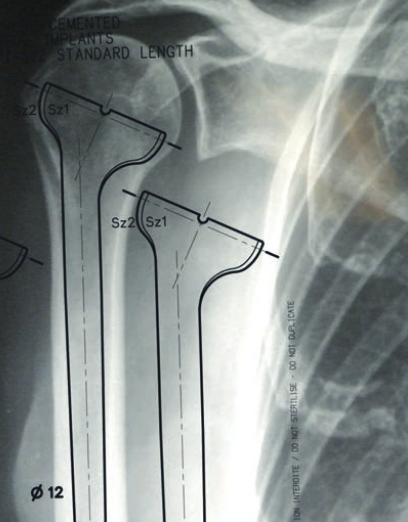

Templating

Xray

Template size and fit of glenoid & humeral components

CT templating

Zimmer Trabecular metal rTSA CT templating

Zimmer Signature One CT templating pdf